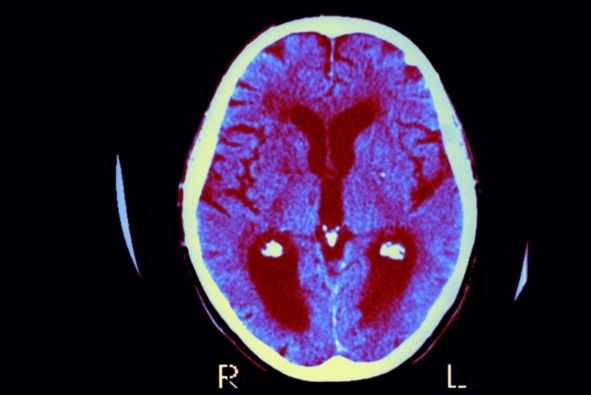

阿尔兹海默症是一种毁灭性的的疾病,目前已有超过500万美国人因此丧失了认知能力和记忆功能,而科学家们一直以来都对其发病根源感到困惑不已。但是在一篇即将发表在《阿尔兹海默症杂志》(Journal of Alzheimer's Disease)上且颇引争议的社论中,一批科学家认为导致这一复杂疾病的病因可能很简单:就是一些能引起脑部感染的微生物。这一引人争议的观点并不新奇,长久以来学界都认为它太过荒诞而不予理会,但是越来越多的工作指出这可能是一个值得考虑并深入研究的方向。如果研究人员能证明这一理论,并且能够解释先前引发争议的某些细节(这两项任务都很艰巨,因为有关脑部感染的研究困难重重),那么人们便能从根本上阻止这一疾病的发生。